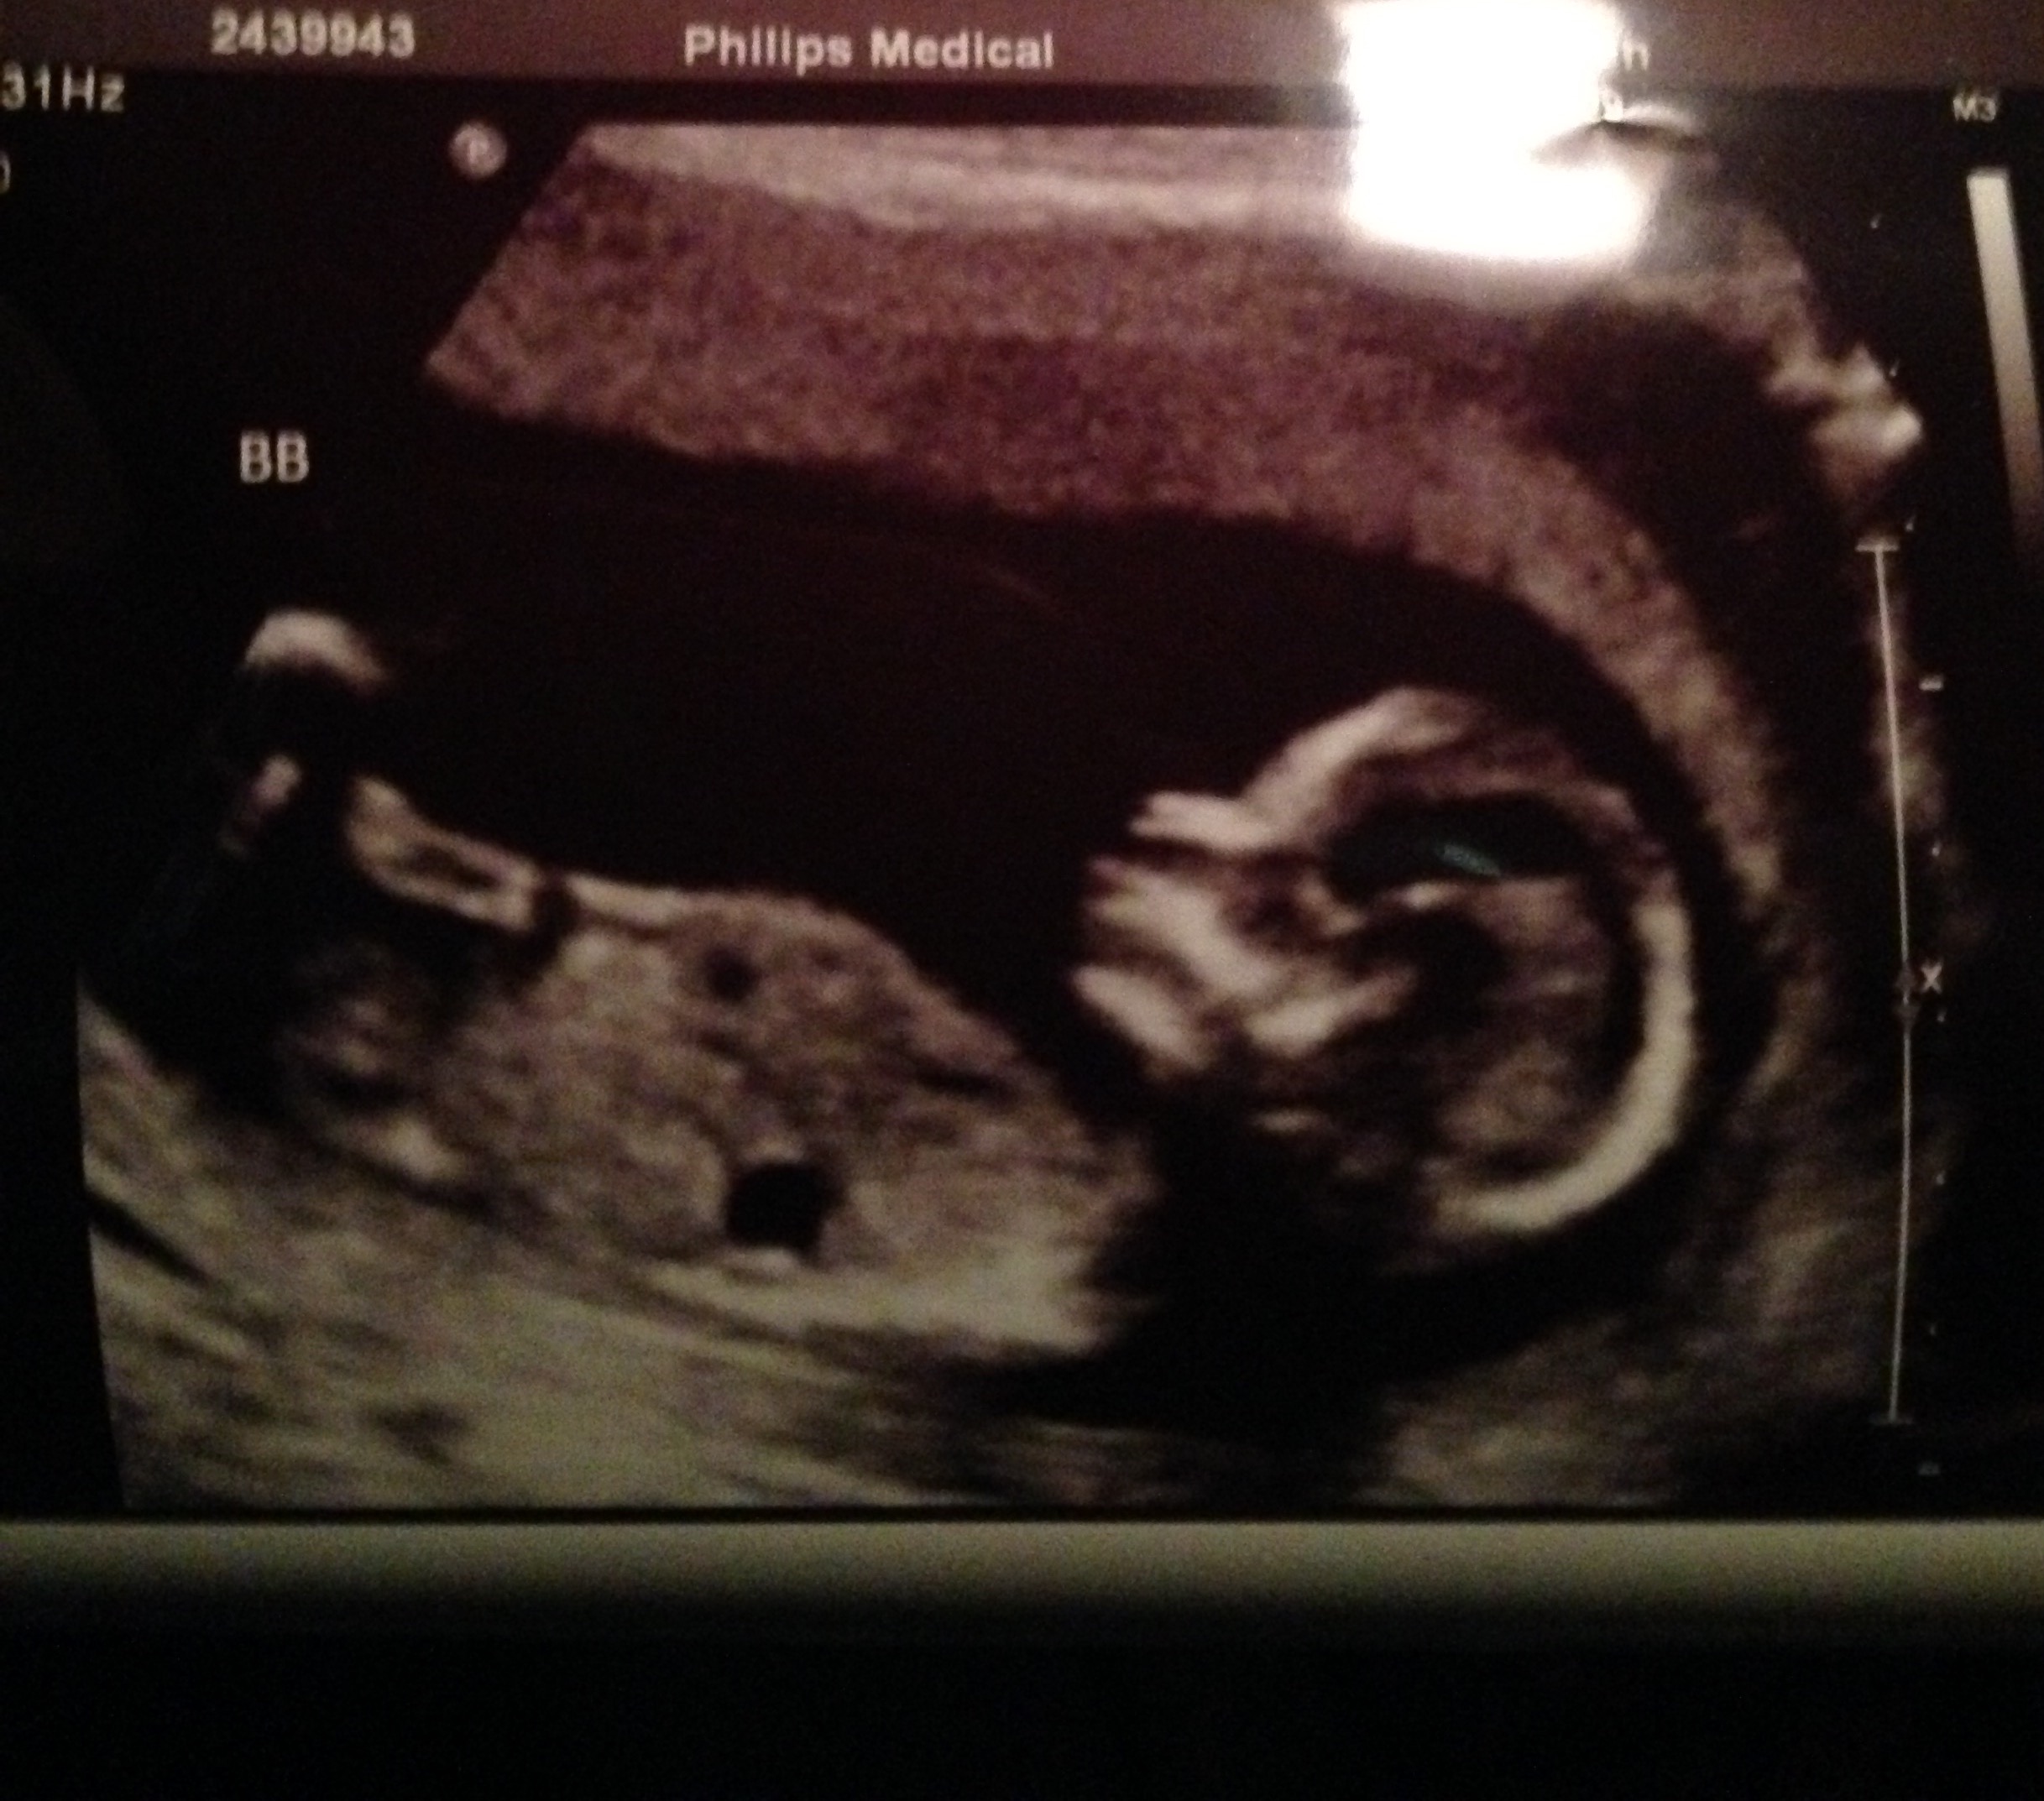

Had an unexpected drs appt monday. Had been having some cramping and spotting off and on since last friday. Turns out everything was fine. But got to see another pic of our baby. Otherwise we wouldn't he gotten another til 20 weeks. So glad that everything is ok, but off my feet til the spotting stops. This was at 13W1D.

Finally getting around to posting our baby bean that actually looks like a baby now at 13w3d. He had an arm up near his mouth and at one point stretched a leg straight up.